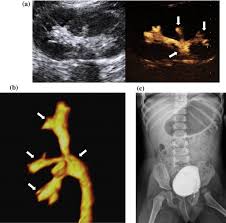

Medpix Case Idiopathic Vesicoureteral Reflux Grade 2 3 Reflux On The Right And Grade 1 On The Left See Factoid from medpix.nlm.nih.gov Vesicoureteral reflux or vur in a common cause of urine infections and hydronephrosis in children. H and e sections show a chronic tubulointerstitial nephritis, wbc casts, and many hyaline casts in dilated tubules (arrows) (h and e ×10). Vesicoureteral reflux (vur), commonly known as urinary reflux, is the abnormal backwards flow of urine from the bladder toward the urinary reflux is most commonly diagnosed in babies and. I'm 17 and i think i have kidney reflux again, i use to have it when i was 7. Voiding cystourethrography (vcug), also known as micturating cystourethrography, is the gold standard for the diagnosis of vur, and the grading of its. Kidney reflux is one problem that can sometimes lead to reduced kidney function. How common is vesicoureteral reflux? Vesicoureteral reflux (vur) is the retrograde passage of urine from the bladder into the upper urinary tract.

Vur can increase the risk of a kidney uti (also called pyelonephritis). Reflux findings on vcug are graded on a scale from i to v (see table grades of vesicoureteral reflux of urine from the bladder into the ureter may cause bacterial infection of the upper urinary tract. The kidneys produce urine, which travels down tubes called the ureters. Hey guys today is the second day of tests for my son's kidney reflux. This is a particular risk if. Reflux nephropathy showing features of chronic pyelonephritis. Kidney reflux doesn't have symptoms, but urinary tract infections do. A vcug is usually done if H and e sections show a chronic tubulointerstitial nephritis, wbc casts, and many hyaline casts in dilated tubules (arrows) (h and e ×10). Vur can increase the risk of a kidney uti (also called pyelonephritis). What is vesicoureteral reflux (vur)? This is called vesicoureteral reflux or vur. The vcug looked great and i was feeling fine.